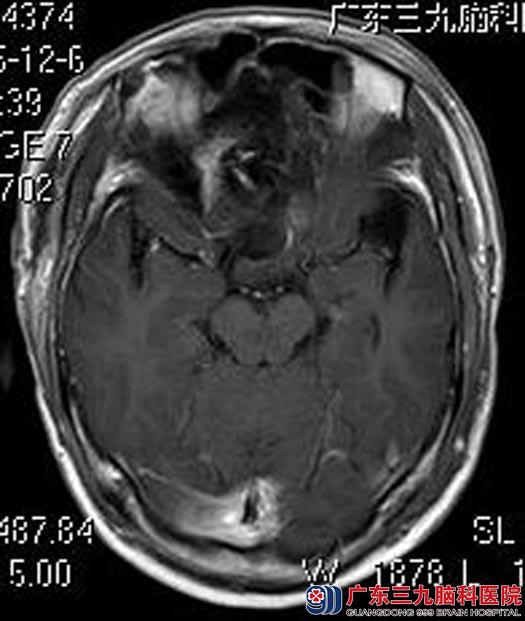

术后,徐先生视物较术前明显好转。术后病理结果提示:脑膜皮细胞型脑膜瘤,WHO I级。

▲术后